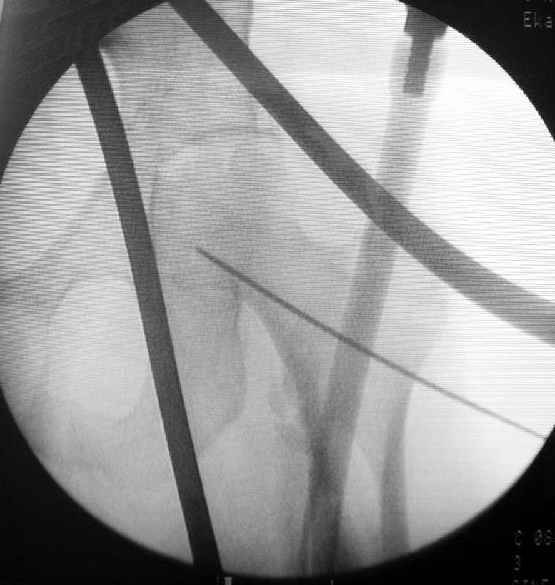

Второй случай тоже репозиция из малого доступа, больному 19 лет, множественные огнестрельные повреждениия конечностей, живота и черепа, правая конечность холодная, без пульсации. Ортопедический диагноз: огнестрельный перелом правого бедра. При срочной ангиографии повреждения сосудов не подтвердилось, конечность из-за ургентности состояния больного зафиксирована временным наружным фиксатором и больной оставлен на операционном столе для срочной лапаротомии хирургической службой.

Больной долго оставался нестабильным, только на 14 день удалось заменить на антеградный интромедуллярный штифт TFN (trochanteric femoral nail) SmithNephew. После неудачной попытки закрытой репозиции, несмотря на использование "joystick", проксимальный стержень от

наружного фиксатора, (перелом начал срастаться) репозицию провели из малого доступа, затем остальные этапы операции.

Случай был представлен из-за того, что больного оперировали после наружной фиксации и был риск инфекцирования через места проведения стержней (на снимках), прошло больше 3 месяцев, выписан из амбулаторной службы из-за отсутсвия надобности дальнейшего наблюдения.